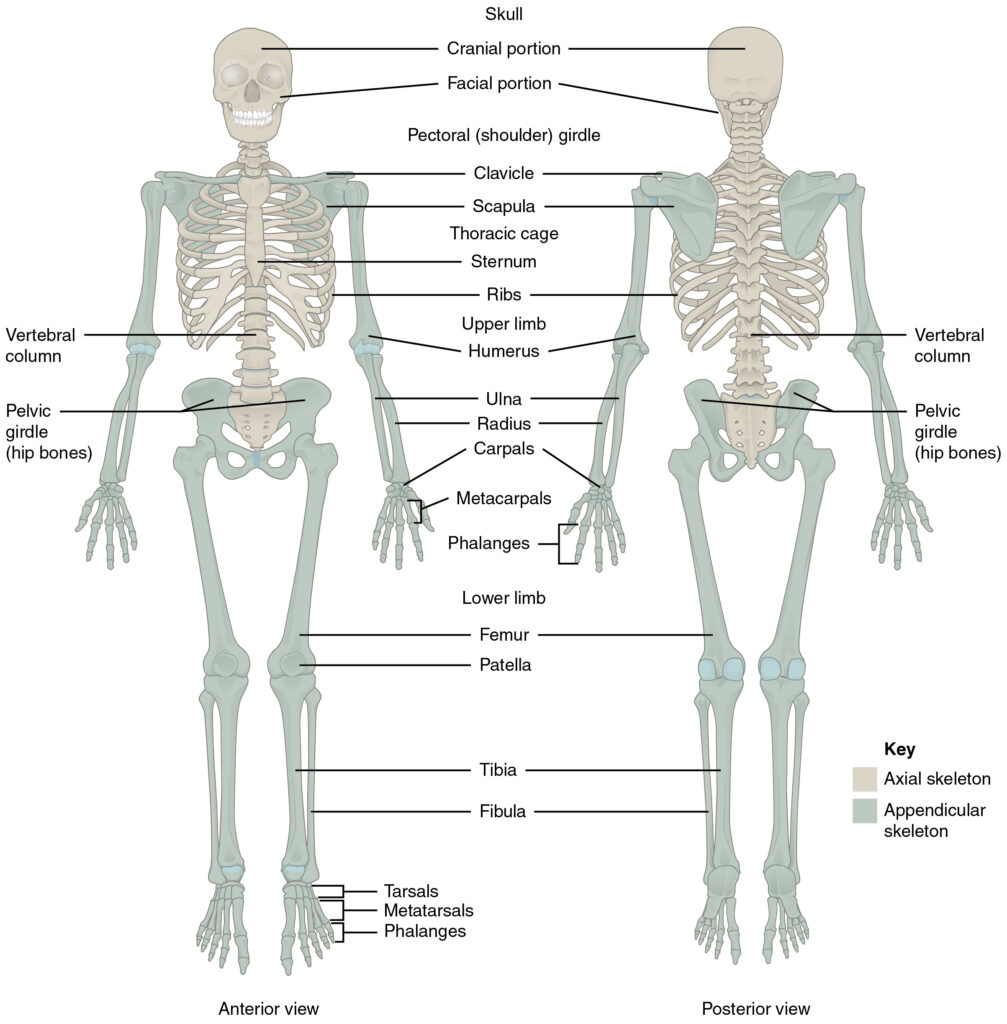

The Skeletal System

The skeletal system—nature’s architectural masterpiece! It’s not just a rigid frame holding you up like coat hangers for muscles and skin. It’s a dynamic, living structure that supports, protects, and even produces crucial elements for your body.

There are 206 bones in an adult human body, but you’re born with about 270. Some fuse together as you grow.

It’s good practice to know some of the main bones in the body; this will help when contacting the emergency services and informing them of possible broken bones.